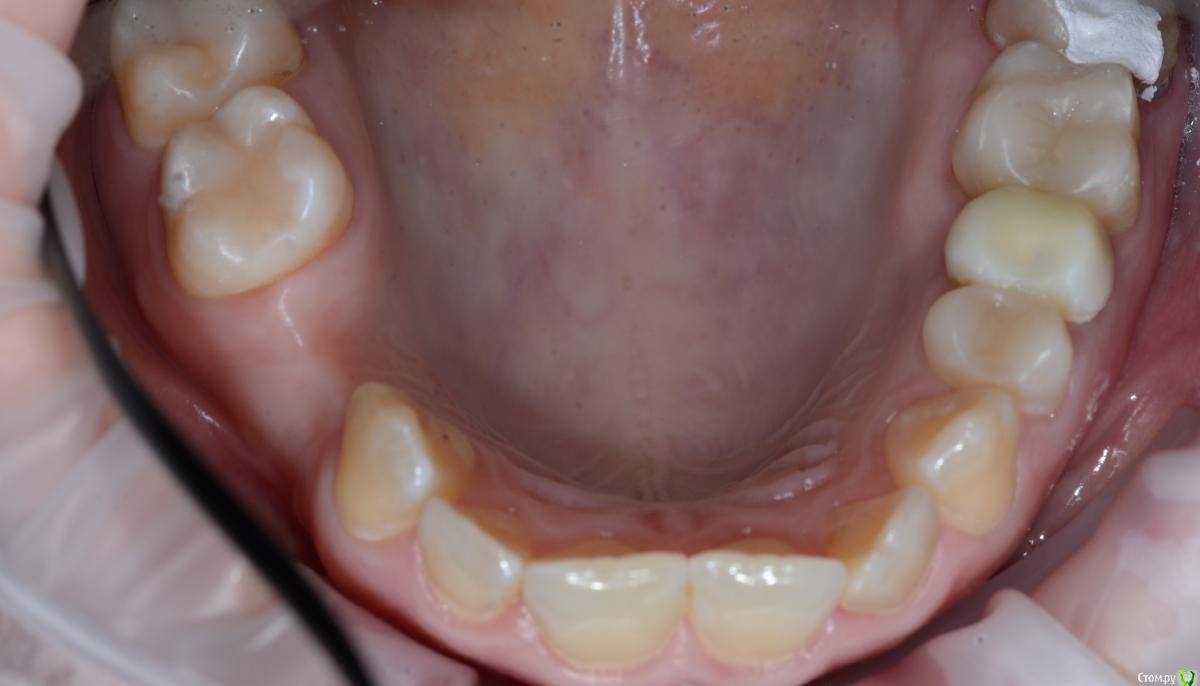

Foxtrot Опубликовано 29 августа, 2018 Поделиться Опубликовано 29 августа, 2018 Доброго времени суток! Как думаете стоит ли устанавливать 2 импланта, удастся ли добиться эстетики мягких тканей? Как бы вы поступили в данной ситуации? У меня пока 3 варианта:1) нкр + импланты - первым этапом, десна - вторым.2) нкр + сст - первым, времянки и еще десна (по ситуации) - вторым.3) 1 имплант, сст, времянка с консолью.Все в один этап как-то страшновато. Ссылка на комментарий

Podarev Опубликовано 29 августа, 2018 Поделиться Опубликовано 29 августа, 2018 Судя по фото пациент девушка. Какие эстетические требования предъявляет? Менее рисково по третьему плану пойти, но готовиться к высокой коронке на 14. В случае широкой улыбки могут возникать вопросы. Теоретически два по 3.0 проходят, но тогда все четко ставить надо Ссылка на комментарий

Foxtrot Опубликовано 29 августа, 2018 Автор Поделиться Опубликовано 29 августа, 2018 Судя по фото пациент девушка. Какие эстетические требования предъявляет? Менее рисково по третьему плану пойти, но готовиться к высокой коронке на 14. В случае широкой улыбки могут возникать вопросы. Теоретически два по 3.0 проходят, но тогда все четко ставить надоДа, вы правы, пациент девушка 30 лет. Эстетические требования - умеренно высокие. По поводу третьего варианта, интересует долговечность конструкции, где-то читал что имеют место быть раскручивания и переломы. Ссылка на комментарий